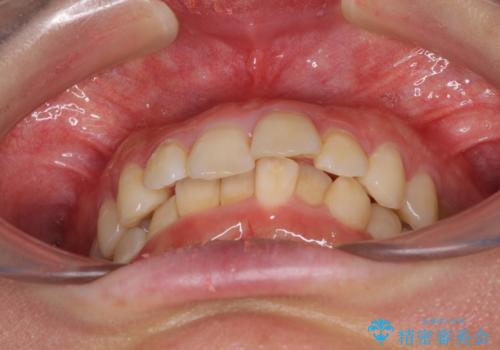

- デコボコの歯列が気になるとことで来院された患者様です。

歯列不正としては軽度であったため、インビザラインでもワイヤー装置でも対応可能でしたが、ご本人の希望によりインビザラインによる矯正治療を行うこととしました。

マウスピース矯正は、自己管理が非常に重要と事前にお伝えしておりましたが、毎日のマウスピース装着が遵守できず、ワイヤー装置での矯正治療へ変更することとなりました。